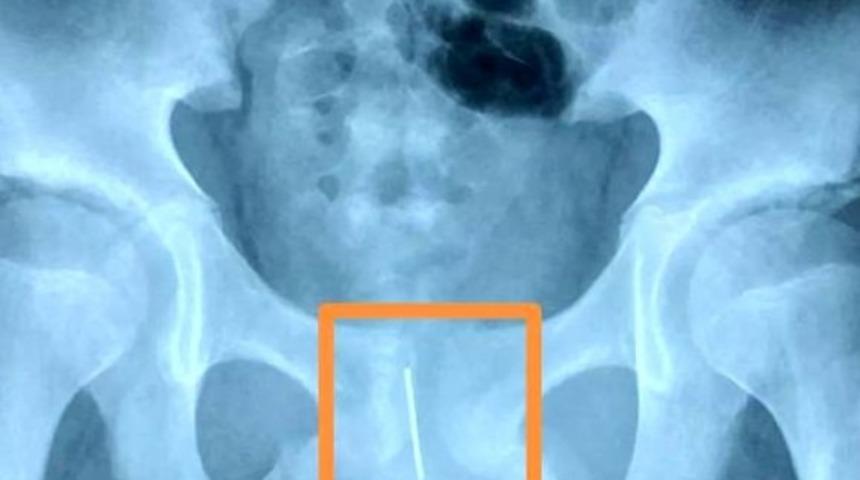

Çin'in Shaanxi eyaletine bağlı Xi şehrinde 12 yaşındaki bir erkek öğrenci, ödevini yetiştirirken uyumamak için cinsel organının içine 11 santimlik bir akupunktur iğnesi koydu. Ertesi gün çocuğunun yürümekte zorlandığını gören anne, oğlunu hastaneye götürdü ve korkunç gerçeği öğrendi.

Doktorlar, öğrencinin yaptığı şeyden utandığı için ailesine söylemekten çekindiğini, bu yüzden cinsel organındaki iğne ile 15 saat durduğunu ve iğnenin idrar torbasına çok yakın olduğunu belirtti. Öyle ki iğne, biraz daha hareket etmesi halinde 12 yaşındaki öğrencinin idrar torbasını yırtabilirdi.

İki saat süren bir ameliyattan sonra doktorlar iğneyi çıkarmayı başardılar. Çocuğun durumunun iyi olduğu belirtildi.